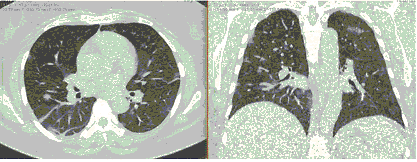

2. Наличие клинических проявлений, указанных в п. 1, в сочетании с характерными изменениями в легких по данным компьютерной томографии (КТ) (см. Приложение 1 настоящих рекомендаций) вне зависимости от результатов однократного лабораторного исследования на наличие РНК SARS-CoV-2 и эпидемиологического анамнеза.

- Изменения при КТ (рентгенографии), типичные для вирусного поражения (объем поражения минимальный или средний; КТ 1-2)

КТ имеет высокую чувствительность в выявлении изменений в легких, характерных для COVID-19. Применение КТ целесообразно для первичной оценки состояния ОГК у пациентов с тяжелыми прогрессирующими формами заболевания, а также для дифференциальной диагностики выявленных изменений и оценки динамики процесса. КТ позволяет выявить характерные изменения в легких у пациентов с COVID-19 еще до появления положительных лабораторных тестов на инфекцию с помощью МАНК. В то же время, КТ выявляет изменения легких у значительного числа пациентов с бессимптомной и легкой формами заболевания, которым не требуется госпитализация. Результаты КТ в этих случаях не влияют на тактику лечения и прогноз заболевания при наличии лабораторного подтверждения COVID-19. Поэтому массовое применение КТ для скрининга асимптомных и легких форм болезни не рекомендуется.